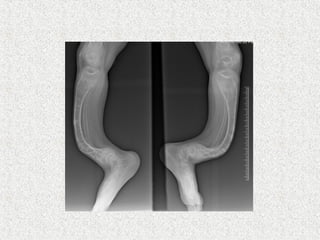

ļ‚ž Anterolateral bow or proximal varus

deformity of the femur

ļ‚ž Anterior or anteromedial bow of the tibia

ļ‚ž Radiograph

ļ‚” Generalised osteopenia

ļ‚” Thinning of long bone

ļ‚” # in various stages of healing

ļ‚” Vertebral compression

ļ‚” Spinal deformity

ļ‚” Skull enlarged

ļ‚” Wormian bones in skull-areas of vicarious

ossification n the calvarium

ļ‚” Widening of metaphysis

ļ‚” Popcorn epiphysis